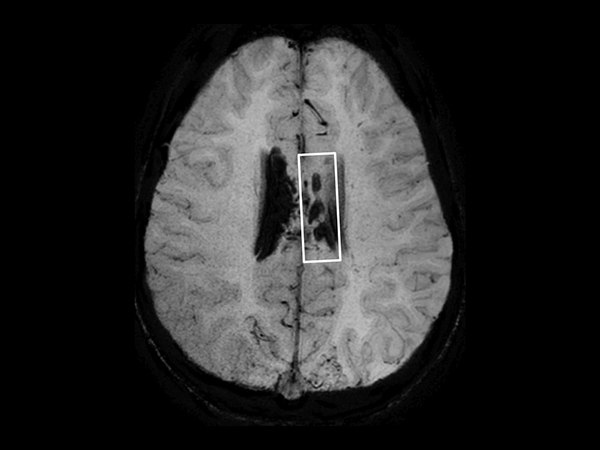

In this case, a 10-year-old girl thrown from a horse. The SWIp images provided increased visibility of the corpus callosum injury compared to the T2-weighted, diffusion weighted and gradient echo images, see the box in the images. SWIp also provides increased visibility of the cortical contusion (arrows) compared to gradient echo imaging. In this case, SWIp helped to characterize the extent of the patient’s injury, which is important to know for short term care and longer term prognosis and rehabilitation.

Axial SWIp